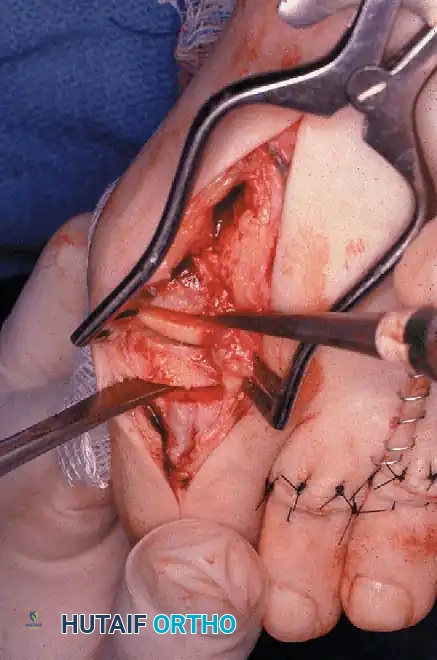

FIBULAR SESAMOIDECTOMY: PLANTAR APPROACH

• If a plantar approach (Fig. 78-21A) is chosen for fi bular sesamoidectomy, have an assistant hold the ankle dorsifl exed, and use a headlight for seeing into the full depth of the wound. Avoid the fl exor hallucis longus tendon and the neurovascular bundle to the fi rst web space.

• Flex and extend the hallux, and inspect the radiograph to locate the sesamoid. Beginning 1 to 1.5 cm distal to the metatarsophalangeal joint, make a longitudinal incision in the plantar surface of the foot, extending the incision proximally 3.5 to 4 cm between the fi rst and second metatarsals.

• If the fi bular sesamoid requires excision, it usually is subluxed.

• When the skin and fascial septa within the forefoot pad have been separated, insert a small self-retaining retractor.

• Using small, blunt-tip dissecting scissors, identify the neurovascular bundle to the fi rst web space, and retract it laterally or medially, depending on the position of the sesamoid (Fig. 78-21B).

• Palpate the sesamoids, and fl ex and extend the hallux to locate the fl exor hallucis longus tendon.

• Open the pulley over the fl exor hallucis longus tendon, and retract the tendon medially. This maneuver is made easier by having an assistant hold the foot in dorsifl exion at the arch with one hand and fl ex the metatarsophalangeal joint to relax the fl exor hallucis longus tendon with the opposite hand.

• At this point, the intersesamoid ligament should come into view; divide it completely (Fig. 78-21C). This may require moving the scalpel 1 or 2 mm laterally or medially to fi nd the groove between the sesamoids.

• Incise the cleavage plane between the two sesamoids, while retracting the fl exor hallucis longus muscle medially and the neurovascular bundle laterally.

• Grasp the fi bular sesamoid with a strong pick-up or small Kocher clamp, and remove the lateral head insertion of the fl exor hallucis brevis muscle on the proximal end of the sesamoid using direct vision (loupe magnifi cation makes this easier, but is not necessary).

• When the medial and proximal restraints of the sesamoid have been released, sever the attachment of the adductor hallucis muscle to its lateral distal edge close to the bone with a scalpel or scissors.

• Sever the last attachment of the sesamoid distally where the plantar plate continues its distal insertion into the proximal phalanx (Fig. 78-21D).

• When the sesamoid has been removed, inspect the wound carefully for any bleeding. Pressing on the edges of the wound helps identify any potential bleeding vessels, which should be cauterized.

• Excising the sesamoid does not release the adductor insertion on the base of the proximal phalanx. This can be released through the plantar incision. Continuing to retract the neurovascular bundle laterally and the fl exor hallucis longus muscle medially, and adducting the hallux, while the opposite index fi nger palpates the adductor, helps identify the structure (Fig. 78-21E).

• Using right-angle retractors, expose the adductor, excise a small section of the tendon, and move the hallux medially.

• At the conclusion of this procedure, the surgeon should be unable to palpate any restraining structures on the fi bular side of the metatarsophalangeal joint. The transverse natatory fi bers in the dorsal aspect of the web space should be released manually. All restraints pulling the hallux laterally (except the extrinsic tendons) must be removed.

• Inspect the neurovascular bundle and the fl exor hallucis longus tendon.*

Fig. 78-21 Fibular sesamoidectomy (plantar approach). A, Incision. B, Common digital nerve to fi rst web space.

Fig. 78-21, cont’d C, Flexor hallucis longus tendon is retracted medially, and neurovascular bun– dle is retracted laterally; intersesamoid ligament is divided. D, Fibular sesamoid ligament is removed, and lateral border of tibial sesamoid is exposed. E, Tendon of oblique head of adductor hallucis. F, Healed plantar incision.